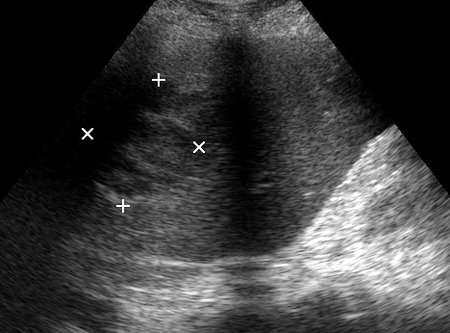

06-12-05-105726_KAZACHENKO-.jpg

06-12-05-105726_KAZACHENKO-.jpg (49.5 КБ) 1487 просмотров

Типичная картина ##1-4:

Гипоэхогенное неоднородное округлое образование, окруженное эхогенным "демаркационным валом"

измененной паренхимы печени.